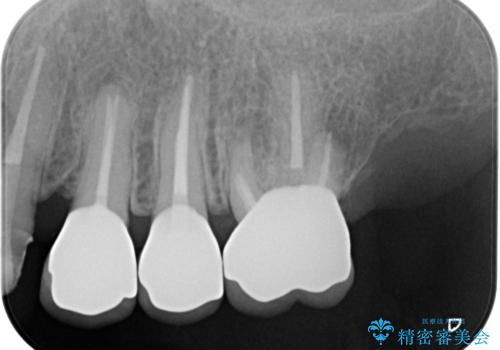

最新の症例

Latest cases